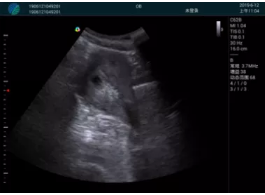

肝內(nèi)血管顯示清晰,血流敏感無外溢